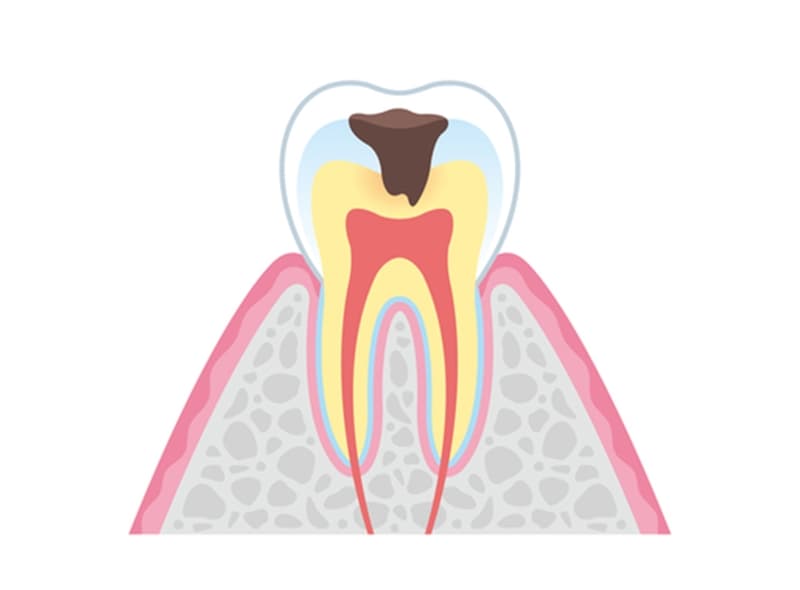

- C2

象牙質のむし歯

むし歯が象牙質に侵入すると、細菌は歯髄に近い部位まで到達します。象牙質は神経との距離が近いため、温度変化などの刺激に敏感になります。この段階では、細菌に感染した歯質を的確に除去し、適切な修復材料で歯を保護することが重要です。